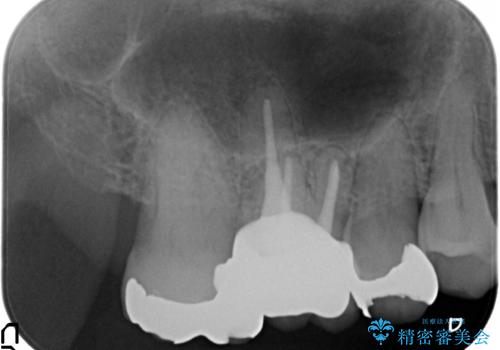

- 右上6番目の銀歯と歯茎の間に隙間ができているのが気になるので診て欲しいといらっしゃった方の症例です。

根管治療も希望されたため、再根管治療終了後、オールセラミッククラウンによる補綴を行いました。